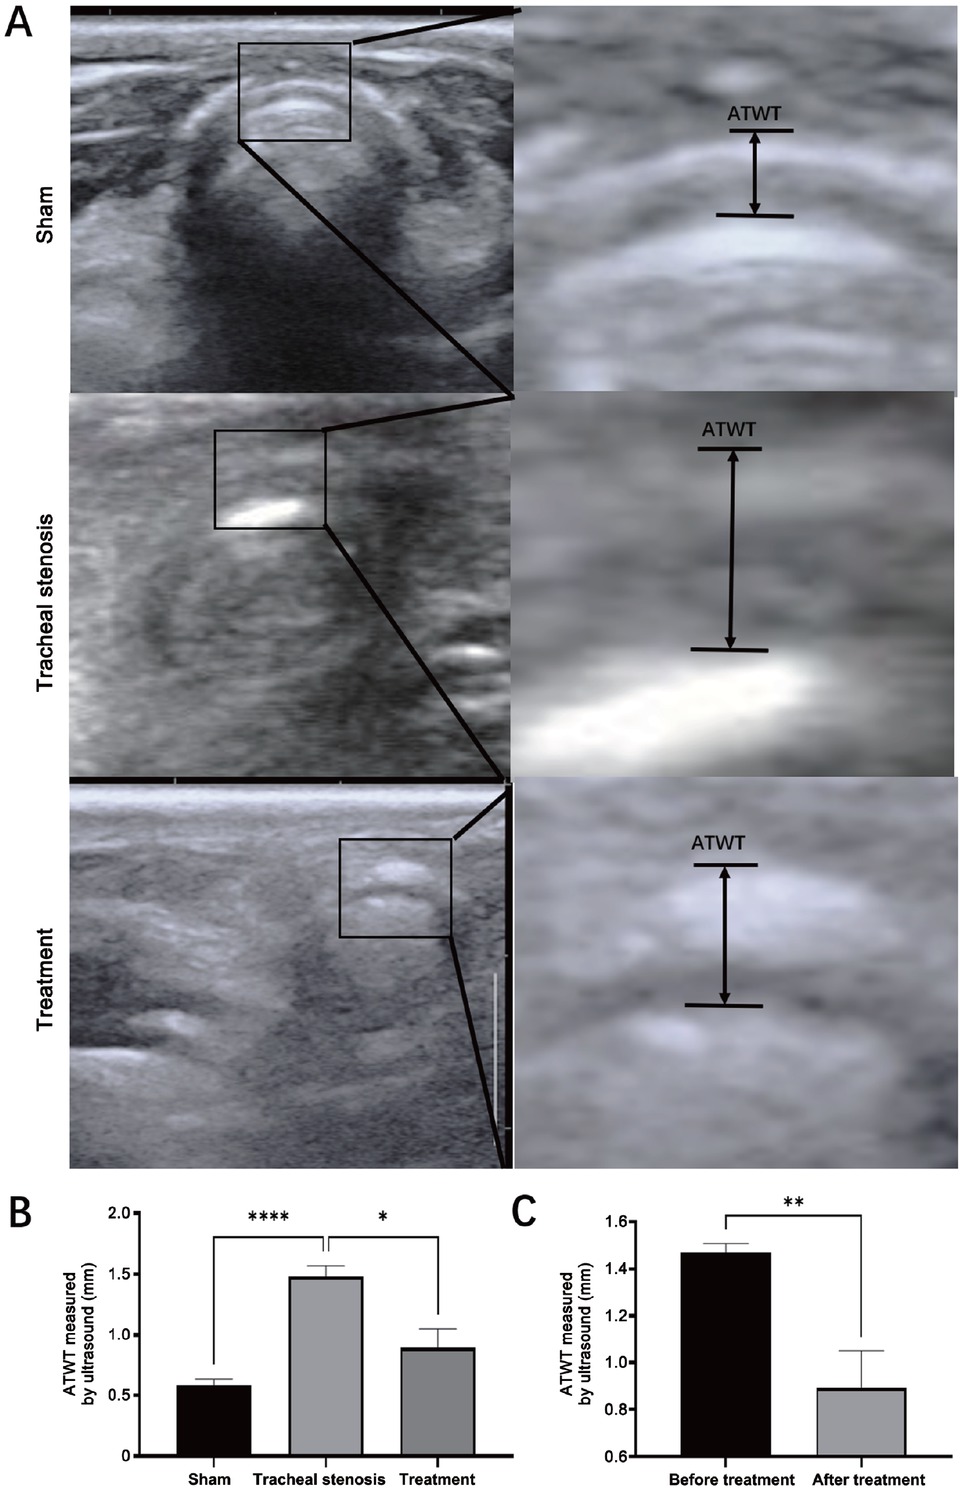

Corresponding to the thickness changes in HE staining, ATWT measured by POCUS presented similar changes, showing increased thickness in the TS model group, while it was significantly decreased in the treatment group (Figure 6).

Comparison of ATWT measured by cervical ultrasound in the transverse plane. (A) Sonogram of the trachea by cervical ultrasound in the transverse plane and measurement of ATWT. (B) Comparison of ATWT in the sham group, tracheal stenosis group, and treatment group. (C) Comparison of the changes of AWAT before and after treatment. Values are expressed as the mean ± SEM (n = 5 rabbits/group). *P < 0.05, **P < 0.01, and ****P < 0.0001. ATWT: anterior tracheal wall thickness; SEM: standard error of the mean.